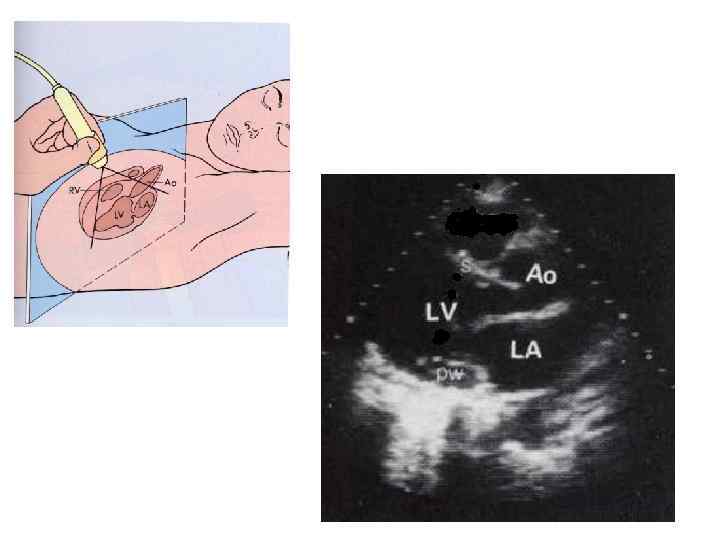

Двухмерная эхокардиография • изображение сердца по длинной оси в реальном времени.

Двухмерная эхокардиография • изображение сердца по длинной оси в реальном времени.